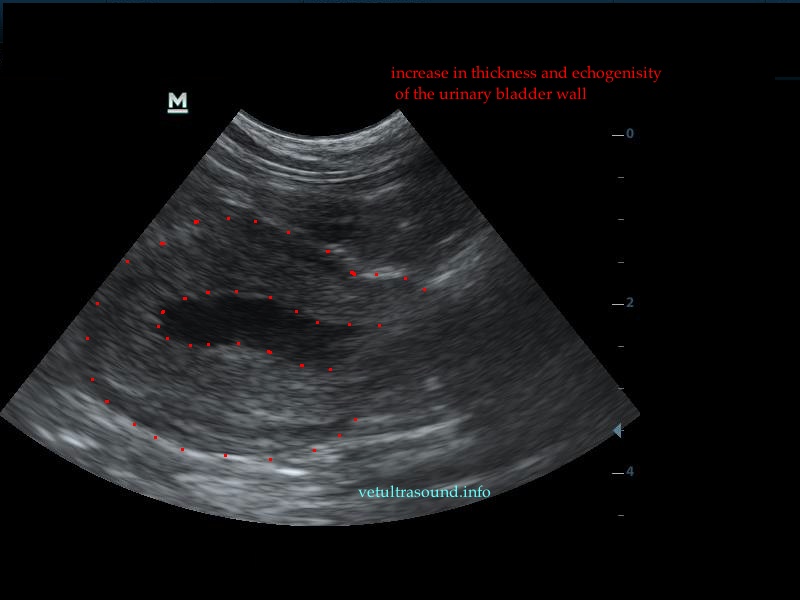

In all the following cases, urinary samples were taken for culture, in order to confirm the diagnosis of bacterial cystitis. In most cases the urinary bladder was almost empty due to polyuria, so we had to wait for about fifteen minutes, with or without the use of furosemide.

The increase of thickness of the urinary bladder wall and the striation of the mucosa is evident. Inguinal lymphnodes are usually prominent and mildly enlarged. Colour Doppler may reveal the blood flow of the mucosa of the empty urinary bladder, whereas the blood flow in a full bladder appears decreased. This could be because of the fibrosis of the urinary bladder wall and could explain why sometimes chronic conditions like these do not respond well to antibiotics. This pathophysiology has been studied in humans with the use of endoscopic ultrasound.